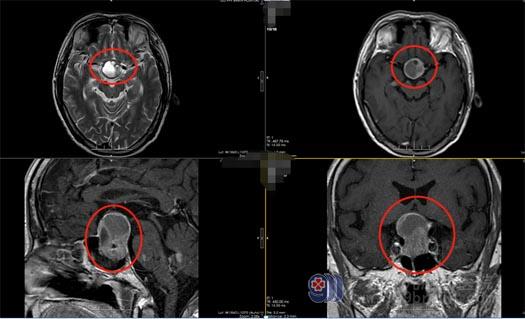

66岁的朱先生视力一向很好。3个月前,他突然发现自己的眼睛只能直直地看到眼前的东西,完全看不到两侧。朱先生到眼科就诊,医生告诉他眼睛没问题,建议去神经外科就诊。在广东三九脑科医院,经CT、核磁共振检查,证实是垂体瘤压迫视神经所致。

垂体瘤是较为常见的颅内肿瘤,垂体是颅内发生肿瘤最常见的部位。垂体的正上方为视神经、视交叉,与垂体相距约1厘米。早期垂体腺瘤常无视力视野障碍,如肿瘤长大,向上伸展,压迫视交叉,则出现视野缺损,以后病变增大,压迫较重,渐渐缺损可扩大至双颞侧偏盲。如果未及时治疗,视野缺损可再扩大,视力也会有减退,以致全盲。因为垂体瘤多为良性,初期病变可持续相当时间,待病情严重时,视力视野障碍可突然加剧,如果肿瘤偏于一侧,可致单眼偏盲或失明。

排除手术禁忌证后,神经外五科医疗团队为朱先生实施内镜经鼻蝶鞍区占位切除术,术中全切肿瘤,无脑脊液漏,出血仅100毫升,未输血,手术完成顺利。术后,朱先生恢复良好,他很满意手术效果,不仅避免了开颅,而且第二天即感觉视力和视野改善明显。